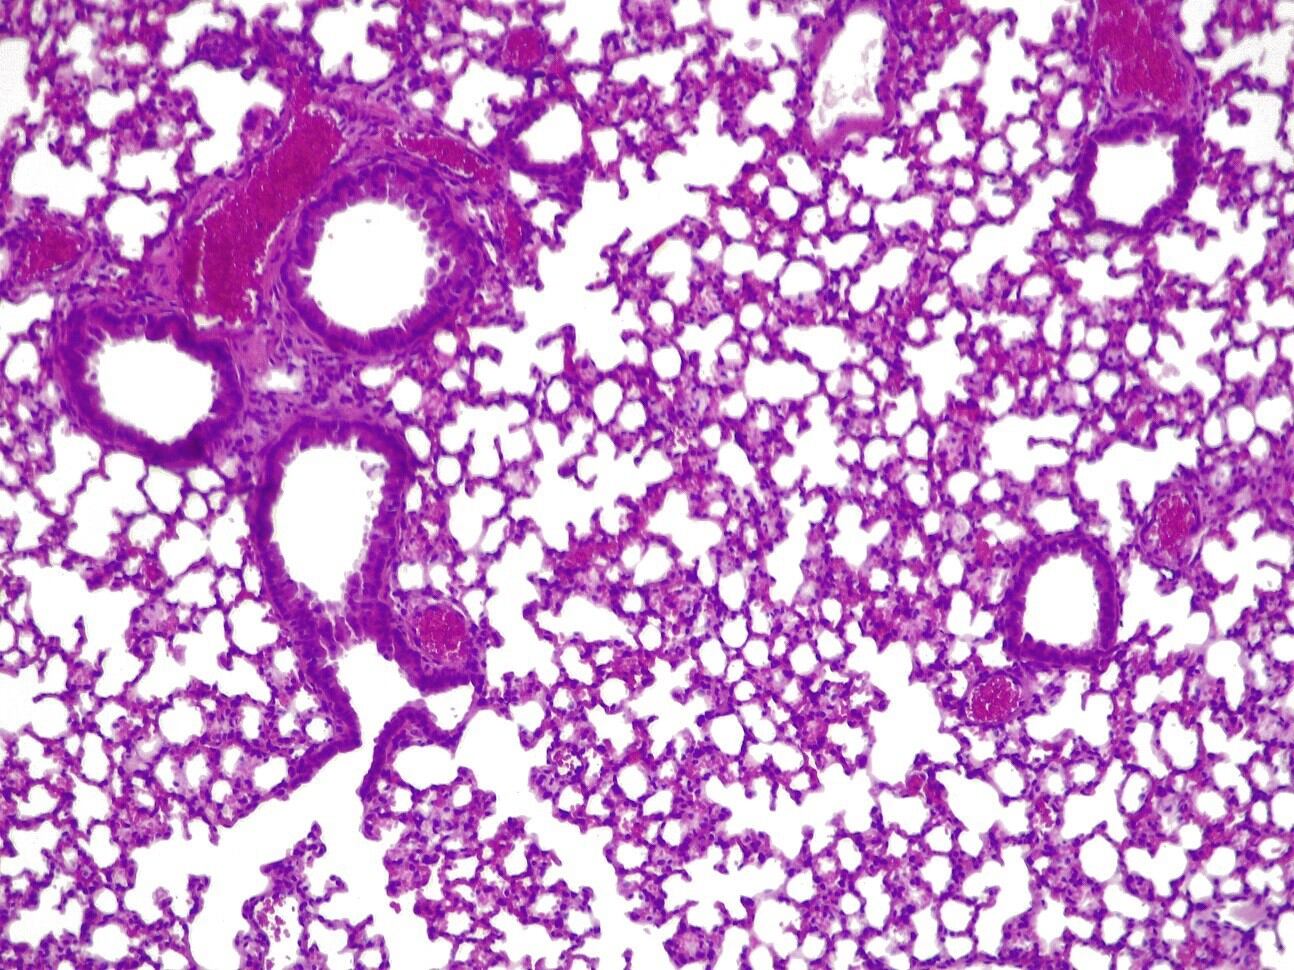

La 'píldora viva' duplicó la tasa de supervivencia del ratón en comparación con la opción de no usar ningún tratamiento, y la administración de una única dosis alta no mostró signos de toxicidad en los pulmones.